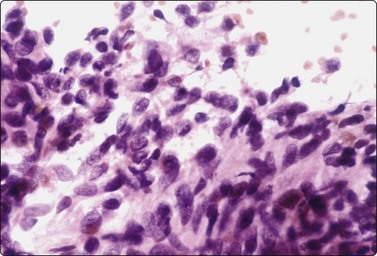

Embryonal carcinoma (Figs 13.33 and 13.34)14,58-61,63,65,66

image image

Fig. 13.33 Embryonal carcinoma

(A) Adenocarcinoma-like tissue fragment of large malignant cells with large vesicular nuclei, coarse chromatin, prominent nucleoli; prominent cytoplasmic vacuolation (MGG, HP); (B) Fragment of undifferentiated mesenchymal tissue right; cluster of malignant epithelial cells with large vesicular nuclei and prominent large nucleoli (H&E, HP) left.

image

Fig.13.34 Embryonal carcinoma

Tissue section corresponding to Fig. 13.33B (H&E, IP).

Criteria for diagnosis

Cell-rich smears,

Frequent three-dimensional clusters,

Occasional tendency to acinar and microglandular grouping,

Large vesicular, obviously malignant nuclei, large nucleoli,

Indistinct cell borders,

Basophilic to amphophilic, sometimes pale, vacuolated cytoplasm,

Immunocytochemistry: cells positive for PLAP, OCT 3/4, CD30, AE1/AE3 and CK7.

The vesicular nuclei of embryonal carcinoma are larger and more pleomorphic than those of seminoma, the chromatin is coarse and irregular and nucleoli are large, occasionally huge, and eosinophilic. The cytoplasm is pale and distinctly vacuolated, but not ‘bubbly’. It is not highly fragile and a TB as in seminoma is not seen. Cytoplasmic boundaries are poorly defined (Fig. 13.33). Hemorrhage and tumor necrosis may be prominent and may hamper the identification of diagnostic cells. It is usually not seen in smears of seminoma. Chromatin threads and reticulated material resembling TB can occur. Large syncytiotrophoblastic cells may be found. Prominent lymphoid/plasma cell infiltrates or mucus are not seen. The presence of cellular mesenchyme on its own does not warrant a designation of teratoma (Figs. 13.33B and 13.34).49